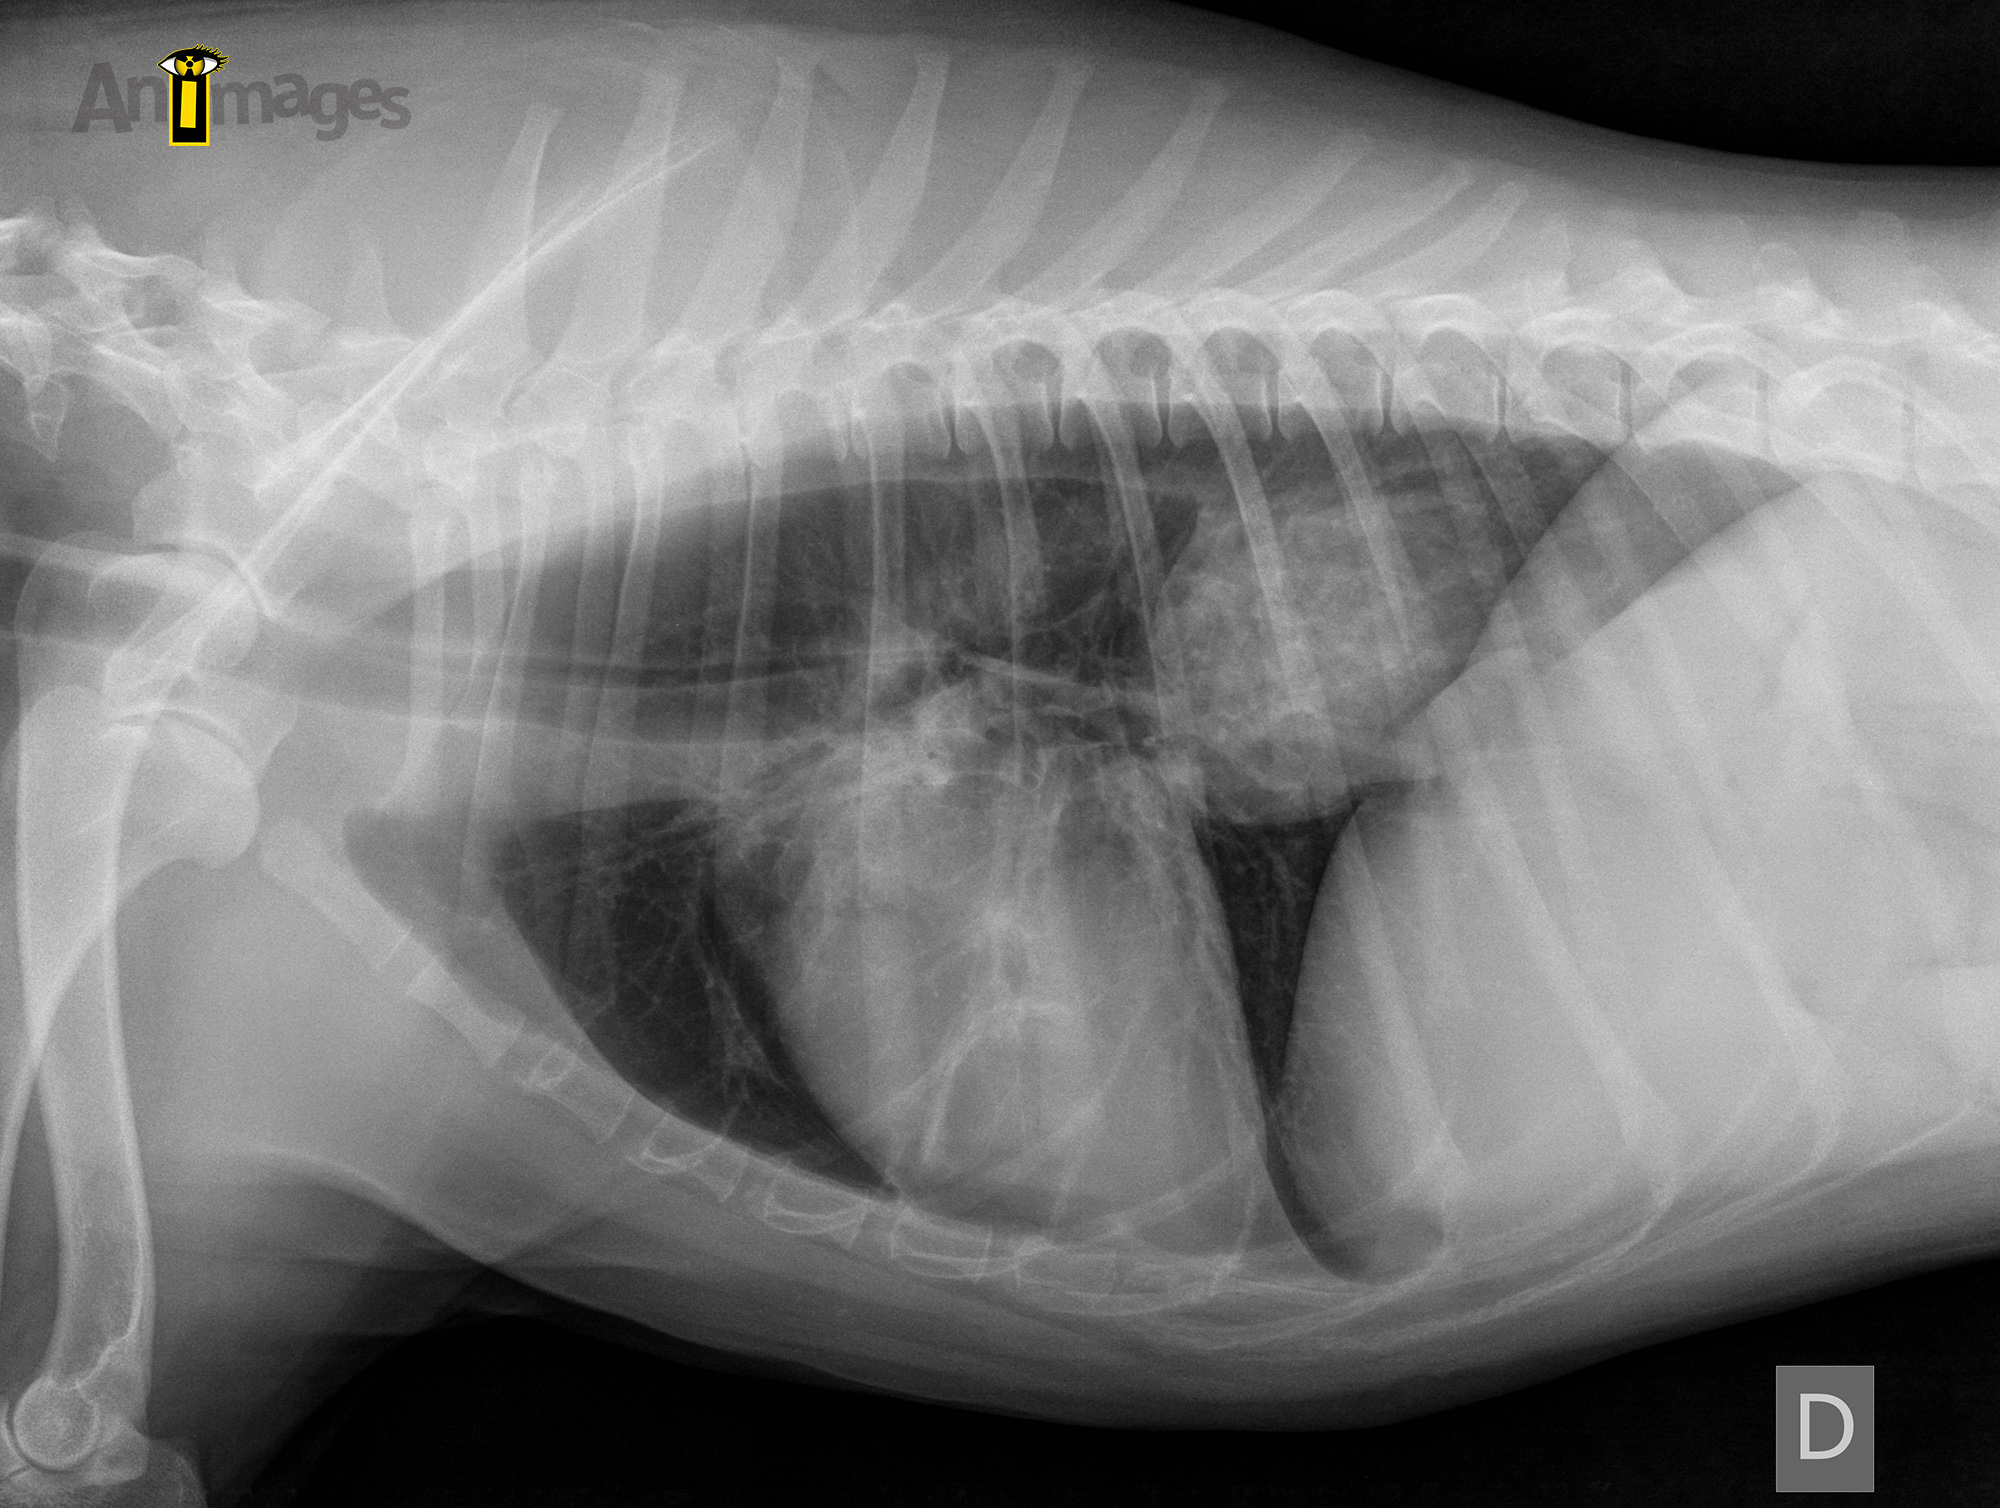

Latérale droite